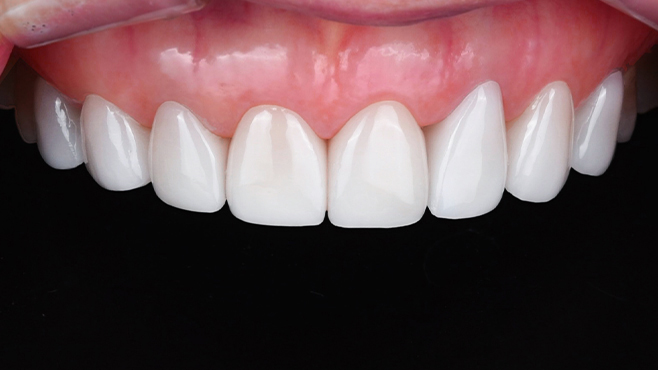

치과가 무서워 10년 동안 미뤄온 임플란트 수술 그 결과는?

2026.01.21